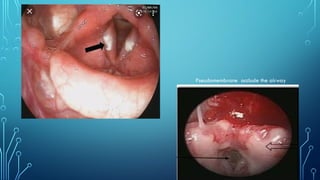

Pseudomembrane occlude the airway

• Membrane. Greyish white membrane is seen on the tonsil, pharynx and soft palate. It is

adherent and its removal leaves a bleeding surface. Similar membrane is seen over the larynx